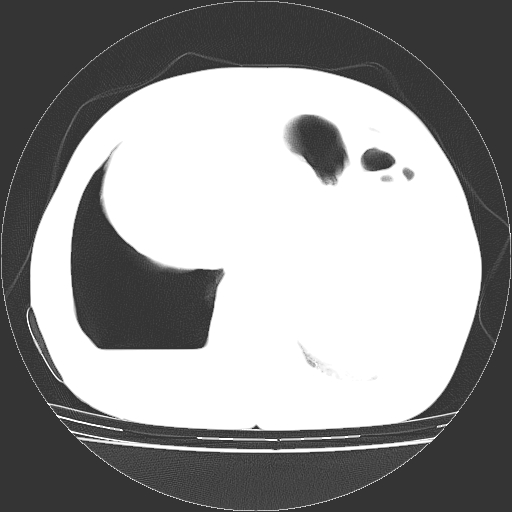

以下是引用zhangzhongshou在2008-3-22 12:52:00的发言:[br]1、右侧液气胸。[br]2、腹水。建议进一步检查。

以下是引用鲁巨ct在2008-3-22 14:10:00的发言:[br]1、右侧液气胸,右中下叶节段性不张。[br]2、腹水,建议上腹部ct检查

以下是引用zjzjr在2008-3-22 17:19:00的发言:[br]1、右侧液气胸,右下叶节段性不张。[br]2、腹水,建议上腹部ct检查